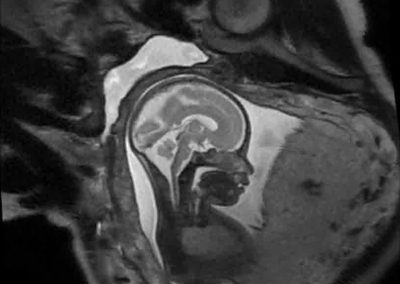

L’Université Paris Cité franchit une nouvelle étape dans le domaine de l’imagerie médicale anténatale avec l’acquisition d’un système d’Imagerie par Résonance Magnétique (IRM) 1,5T ARTIST™ de GE HealthCare. Cet équipement de pointe renforce les capacités de la Plateforme LUMIERE à l’hôpital Necker-Enfants malades, plateforme intégrée de soins, de recherche clinique et d’enseignement en imagerie médicale de la femme enceinte, du fœtus et du placenta.

L’acquisition de cette nouvelle IRM s’inscrit dans le cadre du protocole de recherche « LUMIERE SUR LE FETUS », dont les objectifs sont d’améliorer la prise en charge des pathologies anténatales, d’affiner leur pronostic et de contribuer à la réduction de la morbidité et de la mortalité à court, moyen et long terme. Cette acquisition a été rendue possible grâce au don exceptionnel de la Fondation LUMIERE d’un montant de 250k euros ainsi qu’au soutien de l’Université Paris Cité à hauteur de 670k euros.

Une plateforme au service de la recherche et des patientes enceintes

Depuis 2020, la Plateforme LUMIERE offre aux femmes enceintes volontaires, entre 16 et 36 semaines d’aménorrhée et suivies à l’hôpital Necker-Enfants malades, la possibilité de participer activement à l’avancée de la recherche en médecine fœtale, tout en bénéficiant d’une IRM fœtale au cours de leur grossesse, réalisée dans un cadre sécurisé et encadré.

L’inclusion de ces patientes, depuis leur accueil jusqu’à la réalisation des examens d’imagerie, puis l’analyse des images et l’interprétation des résultats par des équipes expertes, enrichit une base de données structurée, unique au monde, au service de la recherche et de l’innovation en imagerie anténatale et en médecine fœtale.